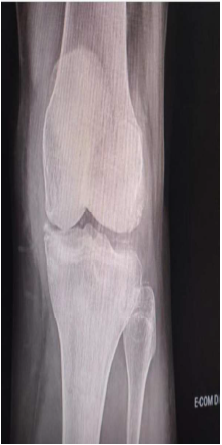

Paciente de 72 anos procura o pronto atendimento com quadro de dor intensa e limitante em joelhos há 48 horas.

Relata episódios prévios de dor e inchaço em joelhos e no punho direito. Ao exame clínico apresenta artrite de joelho esquerdo com derrame volumoso e calor. Abaixo, a radiografia realizada no pronto atendimento.

Fonte: Banca examinadora, 2026.

Com base no quadro clínico descrito e a imagem fornecida, marque a opção correta quanto à hipótese diagnóstica mais adequada.